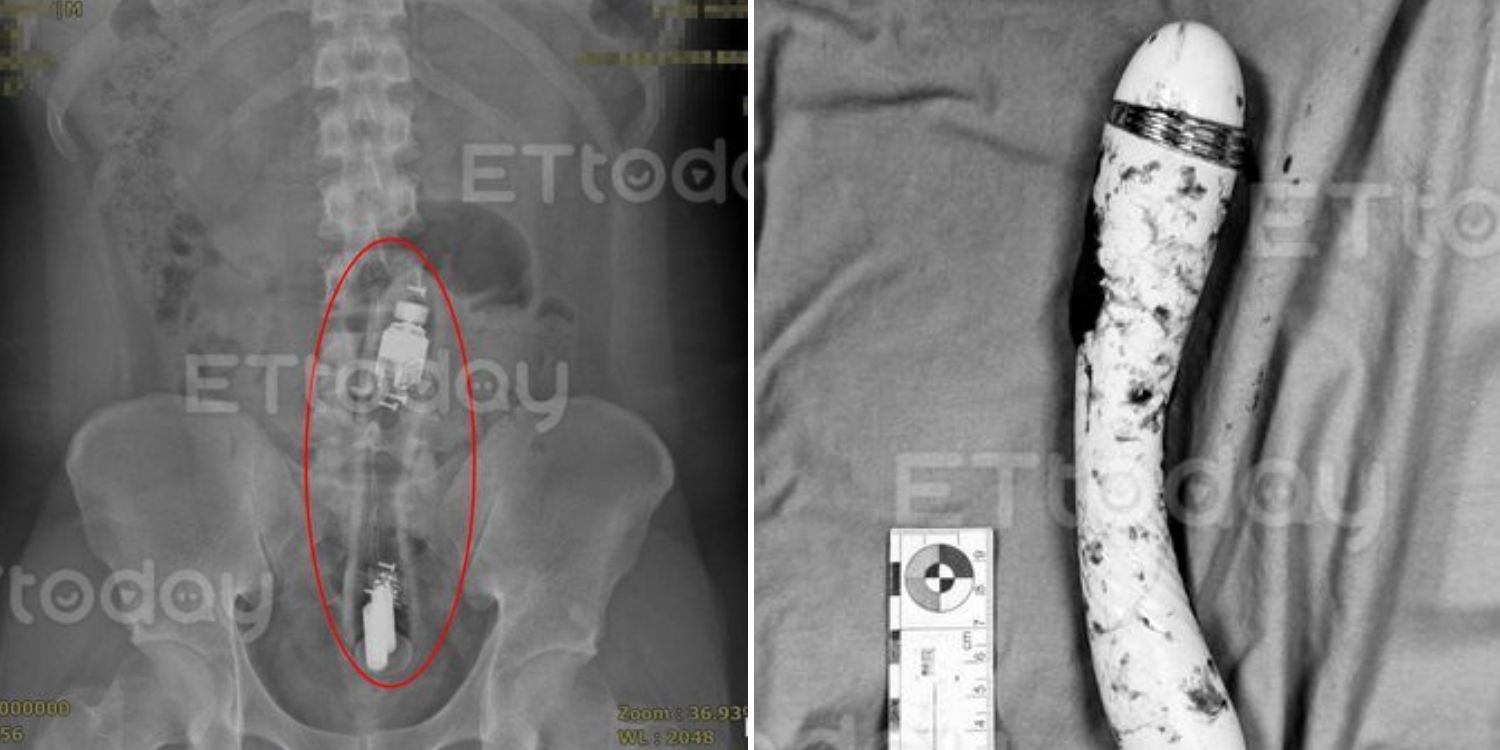

Vibrator removed while still switched on

Remarkably, the man remained calm throughout the procedure, enabling doctors to use forceps, typically used in obstetrics, to extract the vibrator carefully.

Dr Chen recalled that the device was “still slightly vibrating”.

Source: ETtoday

The medical staff were equally astonished that the device’s battery had lasted all night.